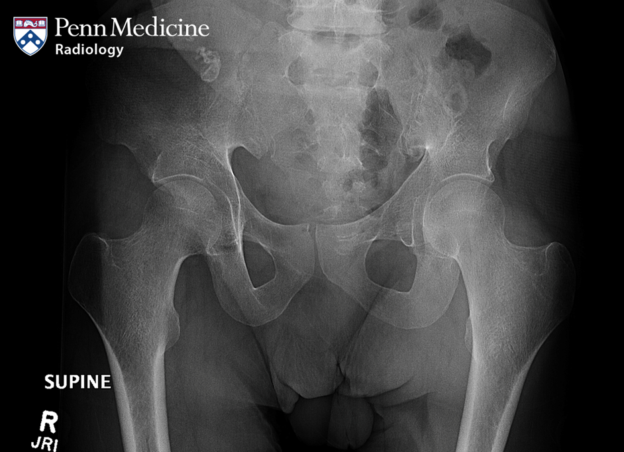

37-year-old man with hip pain after a fall

A 37-year-old man presented to the emergency room with left hip pain after a fall.